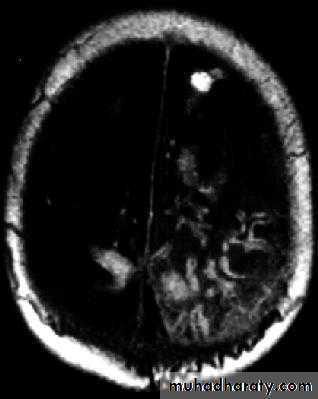

Brain Abscess MRI

Neurosurgery

Brain Abscess

• B. Radiological Investigations:

• The differential diagnosis of a single brain abscess in CT or MRI is a solitary metastasis, primary brain tumour or cerebral infarction.

• The differential diagnosis of multiple brain abscesses is from multiple metastasis and tuberculoma.